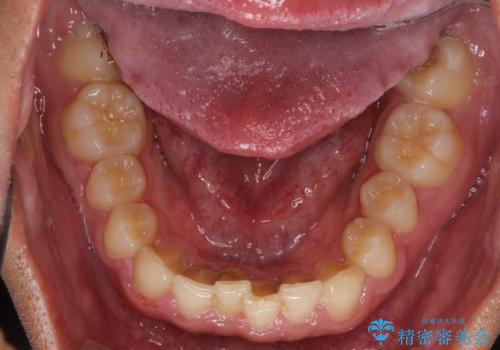

著しいディープバイトと隙間だらけの歯列

- 歯のデコボコと歯の隙間を気にして来院された患者様です。

隙間の原因は、埋伏や前後に重なってしまっている上顎小臼歯と、下の前歯が見えなくなるくらいのディープバイトで、それらを改善する必要がありました。